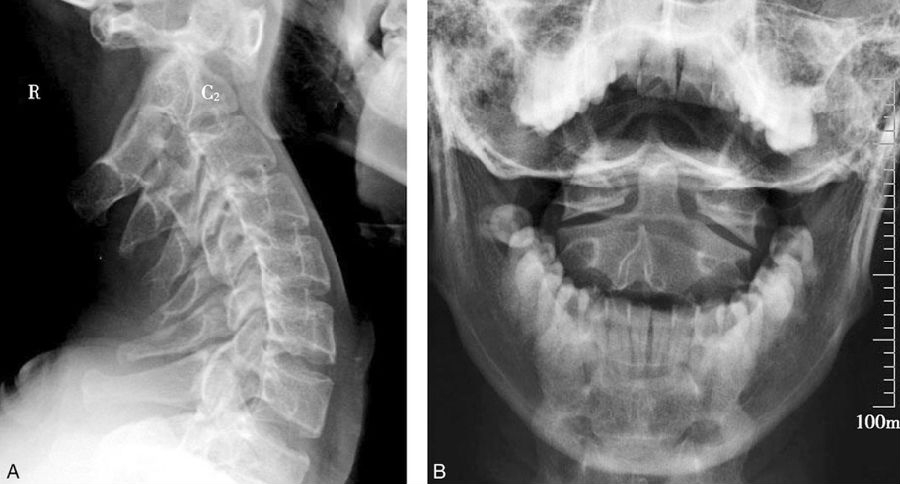

侧位片上,枢椎体部向上伸展形成齿突。寰椎前弓后缘阴影与齿突前缘间形成的间隙称为寰齿前间隙。寰椎前弓前缘阴影投影于其他颈椎总的曲度线之前。枢椎棘突影特别宽大,可作为阅片时颈椎计数的标志(图1)。

颈椎张口位可较满意地观察寰枢椎关节间隙、寰椎侧块和齿突。寰枢椎投影于上下齿列之间,齿突居中央,位于寰椎两侧下关节面最外缘连线的中垂线(寰椎轴线)上。齿突与寰枢椎侧块之间的间隙两侧对称(图1)。

图1 成人寰枢椎侧位(A)及张口位(B)

1. 寰椎前弓;2. 枢椎齿突;3. 寰椎侧块;4. 寰椎后弓;5. 寰齿前间隙;6. 枢椎上关节突;7. 枢椎横突;8. 枢椎椎体;9.枢椎下关节突;10. 枢椎棘突;11. 寰枢外侧关节;12. 寰椎横突。